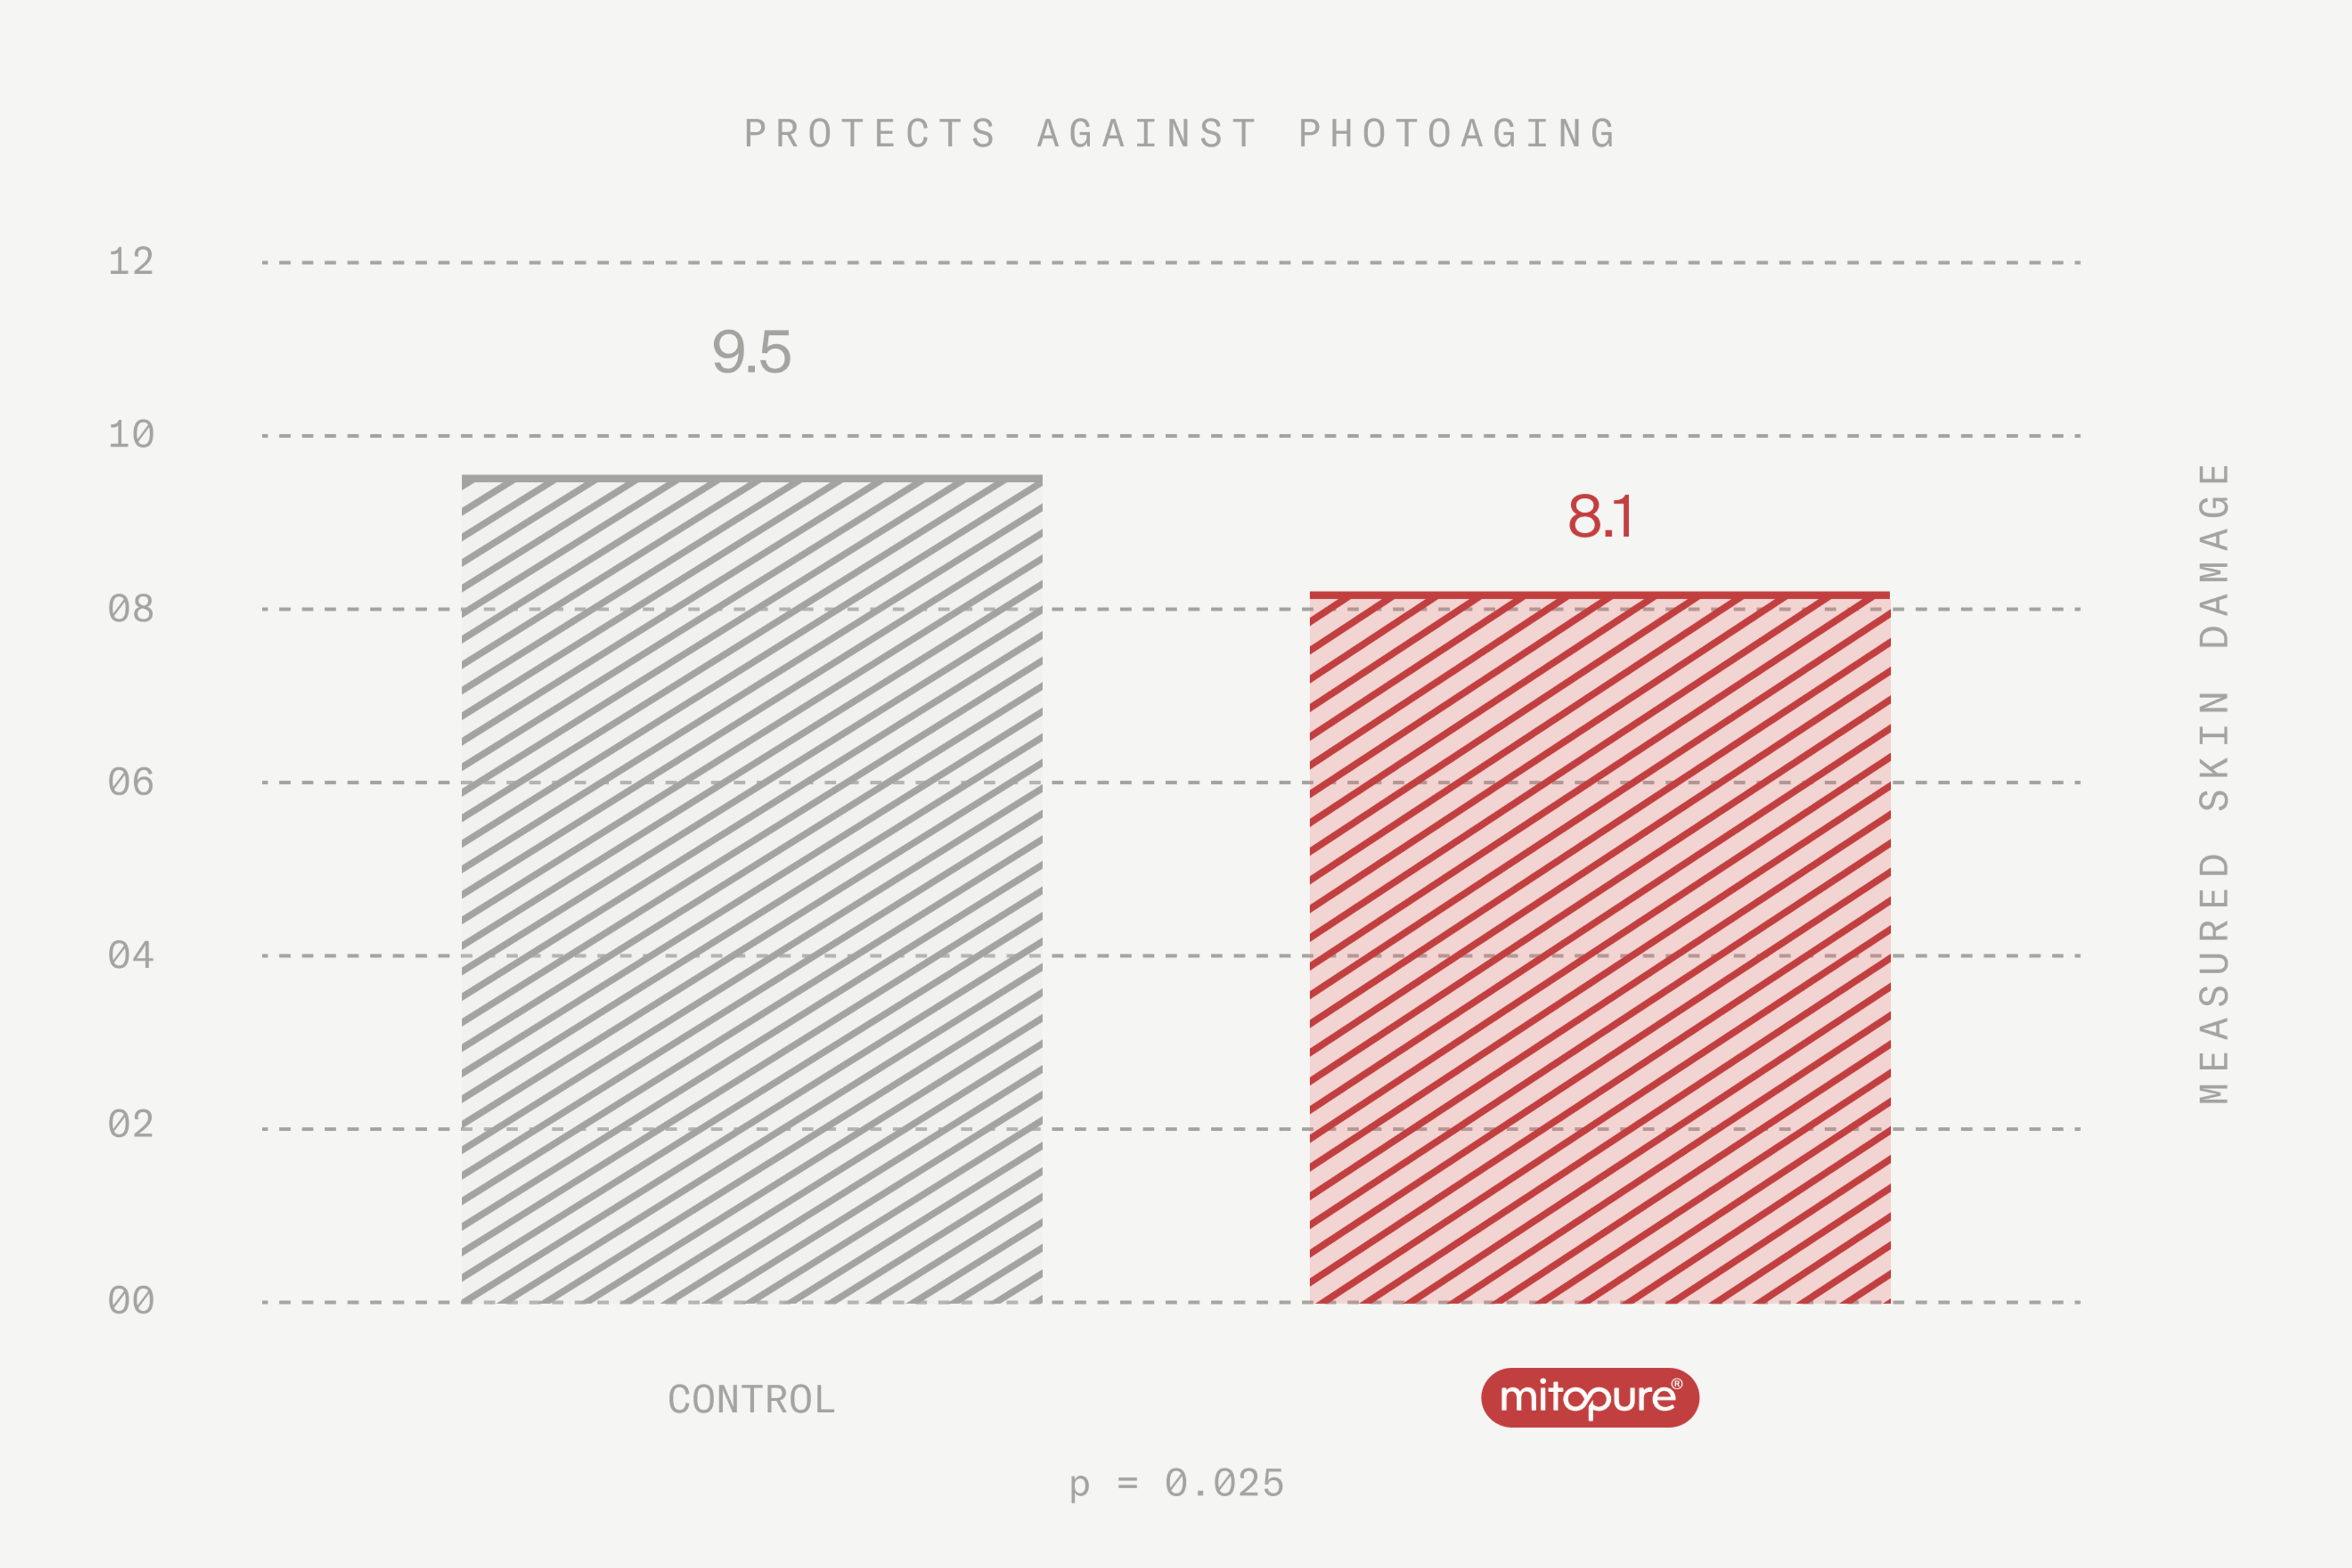

It is clinically proven to support collagen production and assembly, and protect skin from environmental damage (photo-aging)

Mitopure® is clinically proven to help fight off both intrinsic and extrinsic aging factors by supporting collagen assembly and protecting skin from environmental damage (photo-aging).

Mitopure® is also clinically proven to protect skin against the damage from photoaging.